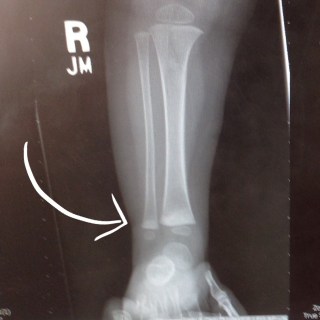

A few days later, our baby with a broken leg wanted to get up and walk. We tried hard for about 24 hours to keep her immobile, but FOR PETE’S SAKE, HAVE YOU EVER TRIED TO KEEP A ONE-YEAR OLD IMMOBILE? It was impossible. We decided to trust her, that she wouldn’t walk if it hurt, and we made an appointment to see a pediatric orthopedic surgeon when we got home, just to make sure her bone was healing properly. Due to some crazy circumstances, we didn’t get in to see the pediatriac surgeon until two weeks after the accident. He took new x-rays, and this is what he showed us:

Clara had, apparently, broken both of the bones in her lower right leg. The tibia and the fibula both had buckle fractures across the same line, probably a result of the way Sam held her tight against him when he fell. The surgeon said if he’d seen her after it happened, he would have cast her leg up to her hip, but it looked like her bones were healing perfectly even without any help, so he wasn’t going to give her a cast at all. It had only been two weeks, and her leg was almost completely healed. She hadn’t broken her growth plate (thank you Lord, that girl is already short enough) and he said she’ll be 100% in no time.

Whew! There you go, the long version of how these adorable x-rays came to be, and of our dramatic introduction to worrying about our children’s health and safety. But I mean seriously, have you ever seen an x-ray that is so damn cute?? Her leg chub, the miniature length of her calf… I melt.